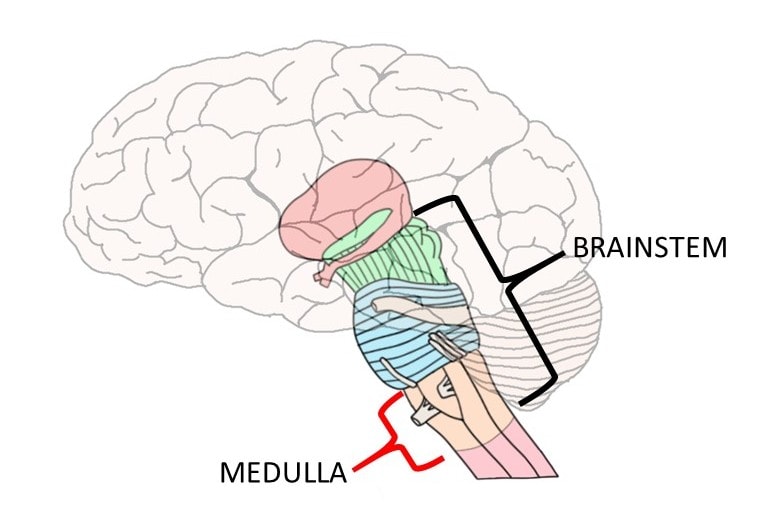

Medulla Oblongata: What It Is, Function & Anatomy

Know Your Brain: Medulla Oblongata

The Anatomy of the Medulla Oblongata

Medulla Oblongata Location, Function, and Features

The Medulla Oblongata and Pons